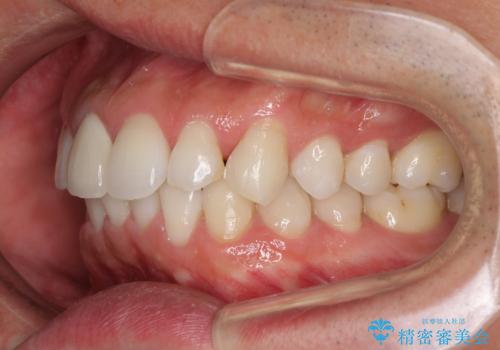

- 口の閉じにくさを気にして来院された患者様です。

患者様と相談の上、横顔の印象から抜歯矯正は必要ないと判断し、IPR(歯と歯の間)並びに歯列全体の後方移動により口元の突出感の改善することとしました。

しっかりと装着時間を守り、ゴムかけも徹底していただいたので、思いの外口元を引っ込めることができました。

これ以上の改善を望まれましたが、非抜歯矯正でこれ以上口元を引っ込めると食いしばりすやすい咬合となるため、この歯列で終了としました。